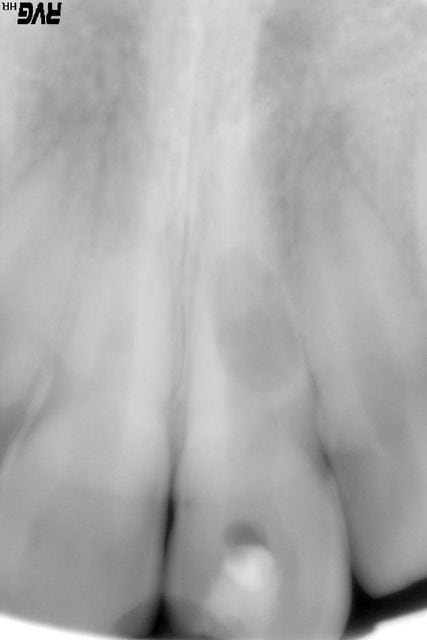

Jeune patiente de 11 ans vient en consultation suite à abces en regard de 21 suite à choc frontal "asymptomatique" en 2002.Désolé, pour la qualité de l'image,sur Trophy c'est plus net.

La dent semble perdue à ce stade de résorption. Tu parles de choc aseptique devenu septique. Je ne pense pas que ce soit le cas. L'image doit pls correcpondre à celle d'une résorption interne post-traumatique.

Il est vrai qu'un traitement endo au MTA pourrait stopper le phénomène inflammatoire et ainsi permettre une conservation de la dent pendant 7 ans avec un peu de chance. Mais faudra que l'enfant évite tout choc sur la dent afin d'éviter une fracture radiculaire du tiers moyen.

je pense à une necrose pulpaire associee visiblement à un granulome interne d'ou l'importante resorption.je pense qu' un parage canalaire 'simpose et d'une obturation a l'hydroxyde calcium pour temporiser.surveillance a une semaine puis 4 , 2mois et 6 mois.tu obture definitivment si tout va bien et couronner par la suite.personnellement, j'aurais fait ca.

et pourquoi pas une resorption externe qui aurait tout traversé?(resorption inflamatoire il me semble)